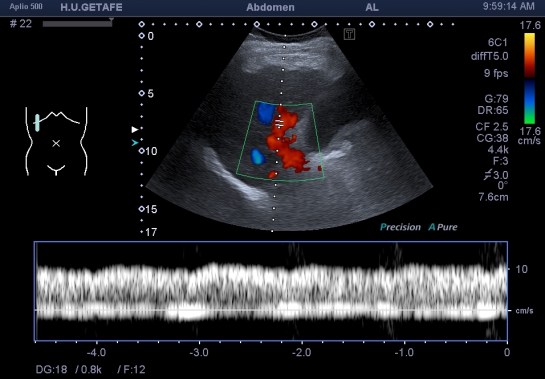

Vascularización portal afectada:

En la imagen 9 quiero que te fijes como el valor de la medida realizada sobre la vena porta estudiada desde transcostal, es demasiado baja para la lectura que habitualmente debe tener dicho vaso, aunque el flujo esté conservado, la medida es importante, podemos reconocer patología en la medida aunque en la imagen la vascularización parezca normal.